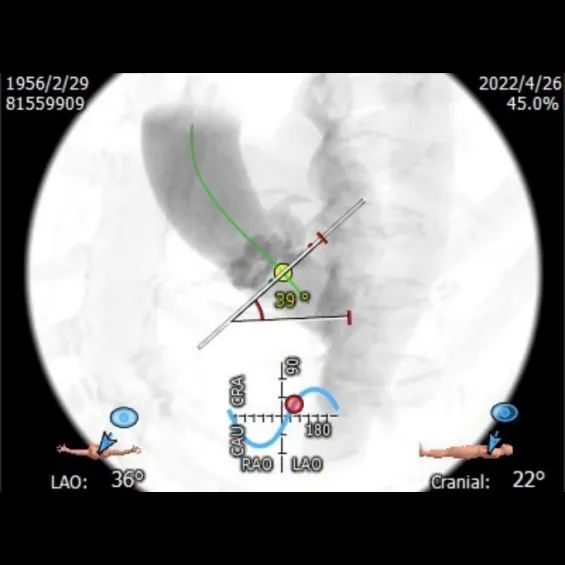

升主内径36.0mm,主动脉瓣环与水平面夹角39°,主动脉弓角与弓距可。

④备TaurusElite AV26和AV29瓣膜。球囊预扩角度LAO 22°,CRA 7°(左冠切线位),跨瓣和释放角度RAO 12°,CAU 24°(左右重合)。瓣膜释放后观察瓣架形态,造影观察瓣周漏和反流情况,综合评估决定是否进行球囊后扩张。